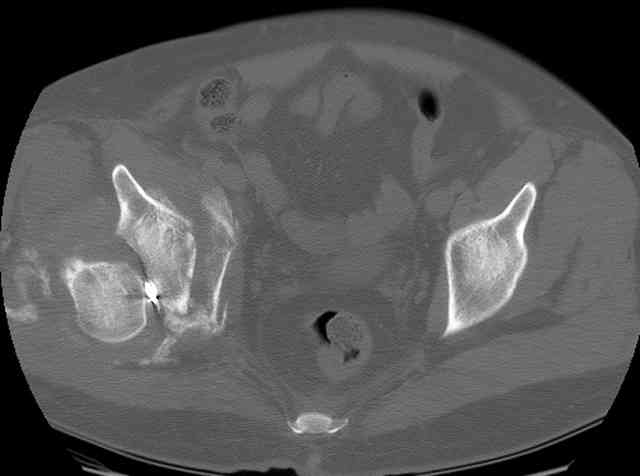

I'll include a few images of a similar injury in a similarly large male patient. This patient "showed up" in our ER c/o hip pain 2 months after being treated in the lateral position, without a quality reduction, without an anterior column transverse supporting implant, with an unbalanced plate applied too medially, with insufficient caudal segment fixation...it took over 8 hours and a 3+ l blood loss to debride the callus from front then

back, excise the HO, release his sciatic nerve, reduce the head-transverse-wall, and fix it...and now it's a staging procedure.

I have another patient 23 years of age, post wall + transverse frx, had surgery 10 months ago elsewere in Ankara without reduction and still has

pain and limp. Hip is posteriorly dislocated and head is destructed by the plates and

screws.